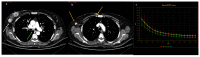

Dual-energy computed tomography (DECT) is one of the most promising technological innovations made in the field of imaging in recent years. Thanks to its ability to provide quantitative and reproducible data, and to improve radiologists' confidence, especially in the less experienced, its applications are increasing in number and variety. In thoracic diseases, DECT is able to provide well-known benefits, although many recent articles have sought to investigate new perspectives. This narrative review aims to provide the reader with an overview of the applications and advantages of DECT in thoracic diseases, focusing on the most recent innovations. The research process was conducted on the databases of Pubmed and Cochrane. The article is organized according to the anatomical district: the review will focus on pleural, lung parenchymal, breast, mediastinal, lymph nodes, vascular and skeletal applications of DECT. In conclusion, considering the new potential applications and the evidence reported in the latest papers, DECT is progressively entering the daily practice of radiologists, and by reading this simple narrative review, every radiologist will know the state of the art of DECT in thoracic diseases.